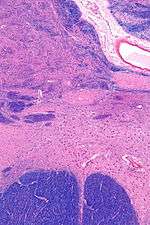

Intermediate magnification micrograph of the nucleus basalis (of Meynert). LFB-HE stain.